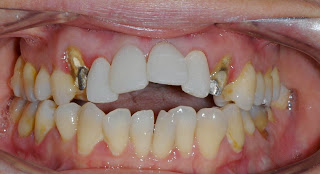

↑正面から見たところ

↑前歯4本が、新しい差し歯になりました。

歯肉が、綺麗なピンク色で、健康的な色になりました。うれしい!

上の写真を見てもらうと分かるけど、実に見事な出っ歯です(笑)!

前歯がボヨーンと突き出てるので、唇が閉じられません。前歯は上の歯と下の歯の間に大きな隙間が出来たので、この状態の前歯で物を噛むのはもう不可能です。